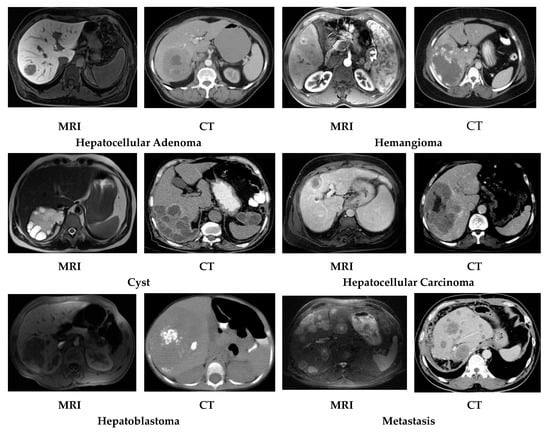

This research comprises a dataset of six classes of liver cancer which are sorted using CT and MR images. An image dataset with two categories of liver cancer was collected. These two categories are: (i) benign liver cancer, which includes a further three subcategories (hepatocellular adenoma, hemangioma, and cyst); (ii) malignant liver cancer, which includes three subcategories (hepatocellular carcinoma, metastasis, and hepatoblastoma), as shown in Figure 1.

Patients suffering from liver cancer were selected as a source of the dataset. The MRI dataset was collected via a Siemens Essenza 1.5T machine with a resolution of 1–2 mm, and the CT-scan dataset was collected via a Siemens Somatom definition-AS 64 machine with a resolution of 0.5–0.625 mm, available in the radiology department of Bahawal Victoria Hospital (BVH) Bahawalpur [20], Pakistan. For each type, 100 patients were selected to examine their liver cancer using CT scan, and 100 patients were examined using MR images of a size of 512 × 512, and a dataset with a total 1200 (100 × 6 × 2) fused (MR and CT) images of liver cancer patients was acquired. All the images were manually examined by an expert radiologist in the light of different medical tests and biopsy reports. Finally, based on a gold standard/ground truth fused liver cancer image dataset, we proposed a novel Otsu thresholding-based region growing segmentation technique.

Figure 1. Typical six liver cancer CT and MR image datasets.